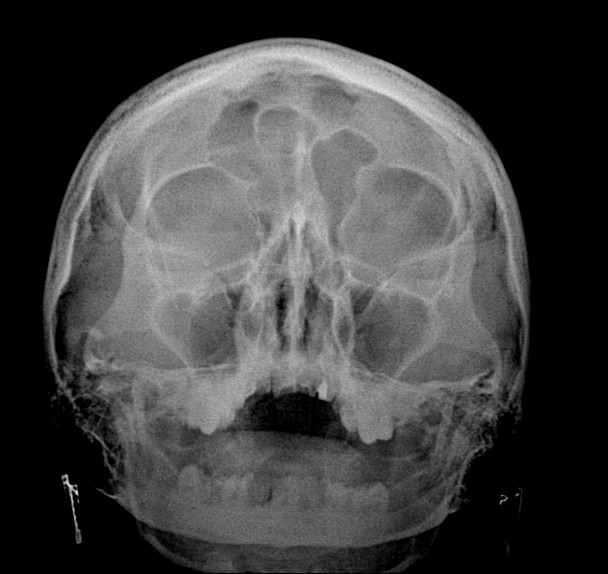

104. Пазухи

Всем привет, подскажите, 1 случай мужчина 75 лет, жалоб нет, идет на операцию, здесь изменения в лобных пазухах могут быть противопоказанием? Что это? 2 случай ребенок 5 лет, гайморовы пазухи...

Область: Челюстно-лицевая область и шея

Модальность: Rg

105. Киста? остеома?

Всем привет, подскажите .1 случай,мальчик 17 лет, лобной пазухе киста? или остеома? 2 случай ,девушка 29 лет, жалобы головную боль, пневматизация лобных пазух сохранена?